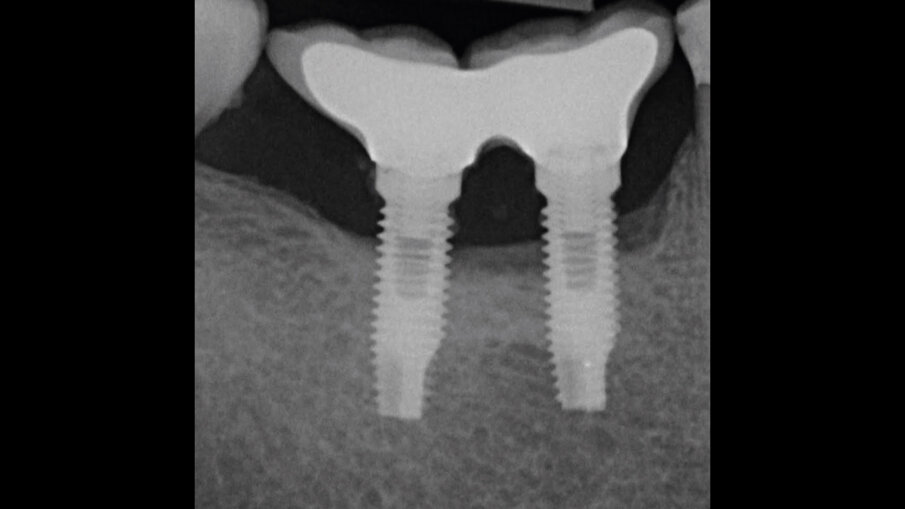

Il paziente, di sesso maschile e di 48 anni di età, è in buone condizioni di salute generale ma, a distanza di 10 anni dall’inserimento, presenta due impianti endossei, in posizione 4.6 e 4.7 con uniforme perdita ossea e con sondaggi di profondità variabile tra 6 e 9 mm accompagnati da sanguinamento, con tessuti marginali che mostrano importanti aspetti infiammatori, causa di sintomatologia dolorosa per il paziente (Figg. 1a-f).

I siti interessati sono stati strumentati per via non chirurgica, utilizzando strumenti manuali, strumenti ultrasonici e air polishing con eritritolo. Al termine della seduta è stato applicato il gel di ozono (Ozosan Gel - Bioactiva) all’interno delle tasche, lasciando agire il dispositivo per 8 minuti, quindi eseguendo lavaggio con soluzione fisiologica. Il post-operatorio ha avuto un decorso privo di dolore con rapida remissione della sintomatologia soggettiva. Il paziente è stato inserito in un programma di mantenimento parodontale trimestrale. A distanza di 6 mesi dal trattamento non chirurgico della perimplantite, i siti si presentano stabili con profondità di sondaggio ridotta tra i 3 e i 5 mm con assenza completa di sanguinamento al sondaggio (Figg. 1g-m).